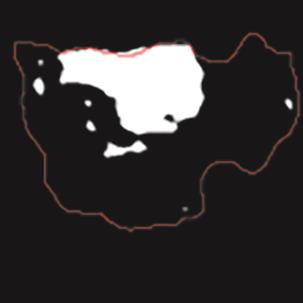

乳腺癌是全球女性最常见的恶性肿瘤之一,准确的病变分割对于乳腺癌的早期诊断与治疗具有重要意义。然而,由于病变形态的多样性以及超声成像机制的复杂性,现有基于深度学习的乳腺超声图像病变分割方法在分割准确性方面仍面临巨大挑战。为进一步提升乳腺超声图像中病变区域的分割精度,该文基于经典U-Net架构,提出了一种新型乳腺超声图像病变分割网络(CWSASKM-BBAM-Net)。首先,在网络中引入逐通道空间自适应选择核卷积模块(CWSASKM),根据不同通道的语义特征为每个空间位置自适应选择感受野大小,以增强多尺度信息的建模能力;然后,引入双向边界感知机制(BBAM),通过融合正向与反向注意力,对目标显著区域及其边界进行协同建模,同时逐步提升对非显著区域与病变区域的区分能力,以进一步强化边界信息的表达;最后,在3组公开乳腺超声图像数据集(BUSI、UDIAT和STU)上开展分割实验。结果表明:该方法在数据集BUSI上的杰卡德指数、精确率、召回率和Dice相似系数分别为71.97%、82.85%、81.40%和80.44%,较次优方法分别提升1.69、1.05、1.28和1.84个百分点;在数据集UDIAT上,这4项指标分别达到78.14%、88.31%、86.73%和86.10%,较次优方法分别提升了2.75、2.04、0.56和2.01个百分点;在外部数据集STU上,该方法也取得了优于其他方法的整体表现。实验结果表明,CWSASKM-BBAM-Net在乳腺超声图像分割任务中展现出更优的整体性能。